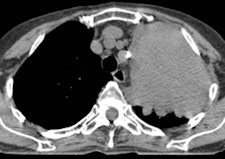

Amount of docetaxel uptake in tumors

An example of a patient with non-small cell lung cancer showing relatively high C-11 docetaxel uptake in a tumor with a volume of 334 cm3. During the therapeutic scan, the patient was treated with 110 mg of docetaxel. Left: CT scan showing tumor. Right: PET/CT fusion image of a therapeutic C-11 docetaxel summed image [25-65 min; mean C-11 docetaxel Ki = 0.0125 mL·cm-3·min-1; total accumulated amount of cold docetaxel at 90 min = 543 µg (at 1.62 µg·cm-3), corresponding with 0.49% of the infused dose docetaxel]. Images courtesy of Dr. Astrid van der Veldt, PhD.A potential problem was that the behavior of 11-C docetaxel in the tumor at tracer doses may be different from its behavior at therapeutic doses, noted van der Veldt. Therefore, she investigated whether a PET study using tracer doses of C-11 docetaxel could predict tumor uptake of docetaxel at therapeutic doses.